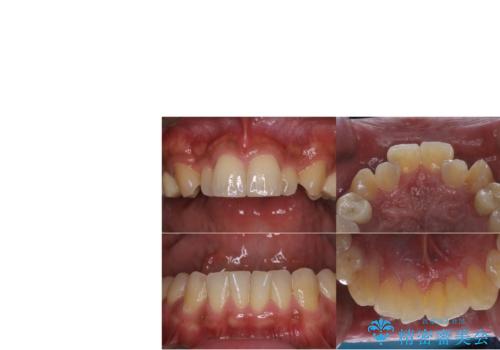

元々噛む力が強く、日常的に歯ぎしりもされるとの事でしたので、歯が割れてしまうリスクを軽減させるため、歯全体を覆うクラウンをメインに補綴治療を行いました。

歯ぎしりや食いしばりの癖がある方にはナイトガードの使用も併せてお勧めしています。就寝時の歯ぎしり食いしばりのコントロールにはボツリヌストキシン注射も有効です。

適合不良の補綴物は二次的な虫歯発生のリスクが高まります。

自費診療で用いられる材料は保険適応の材料に比べて、より精密で適合の良い被せ物作ることができるため、長期的な虫歯のリスクを大幅に減らすことが可能です。